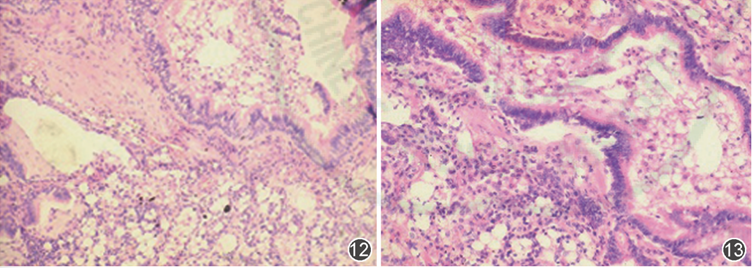

镜下见肺泡上皮及纤维增生,间质大量泡沫细胞,部分泡沫细胞吞噬脂肪颗粒(图4),结合临床病史符合吸入性外源性脂质性肺炎。免疫组化:s100(-),CD68(+),CK(肺泡上皮+),MDM2(小灶+),ki-67(30%+)。特殊染色:脂肪颗粒(-),PAS(-),A/P(-),TB染色(-)。